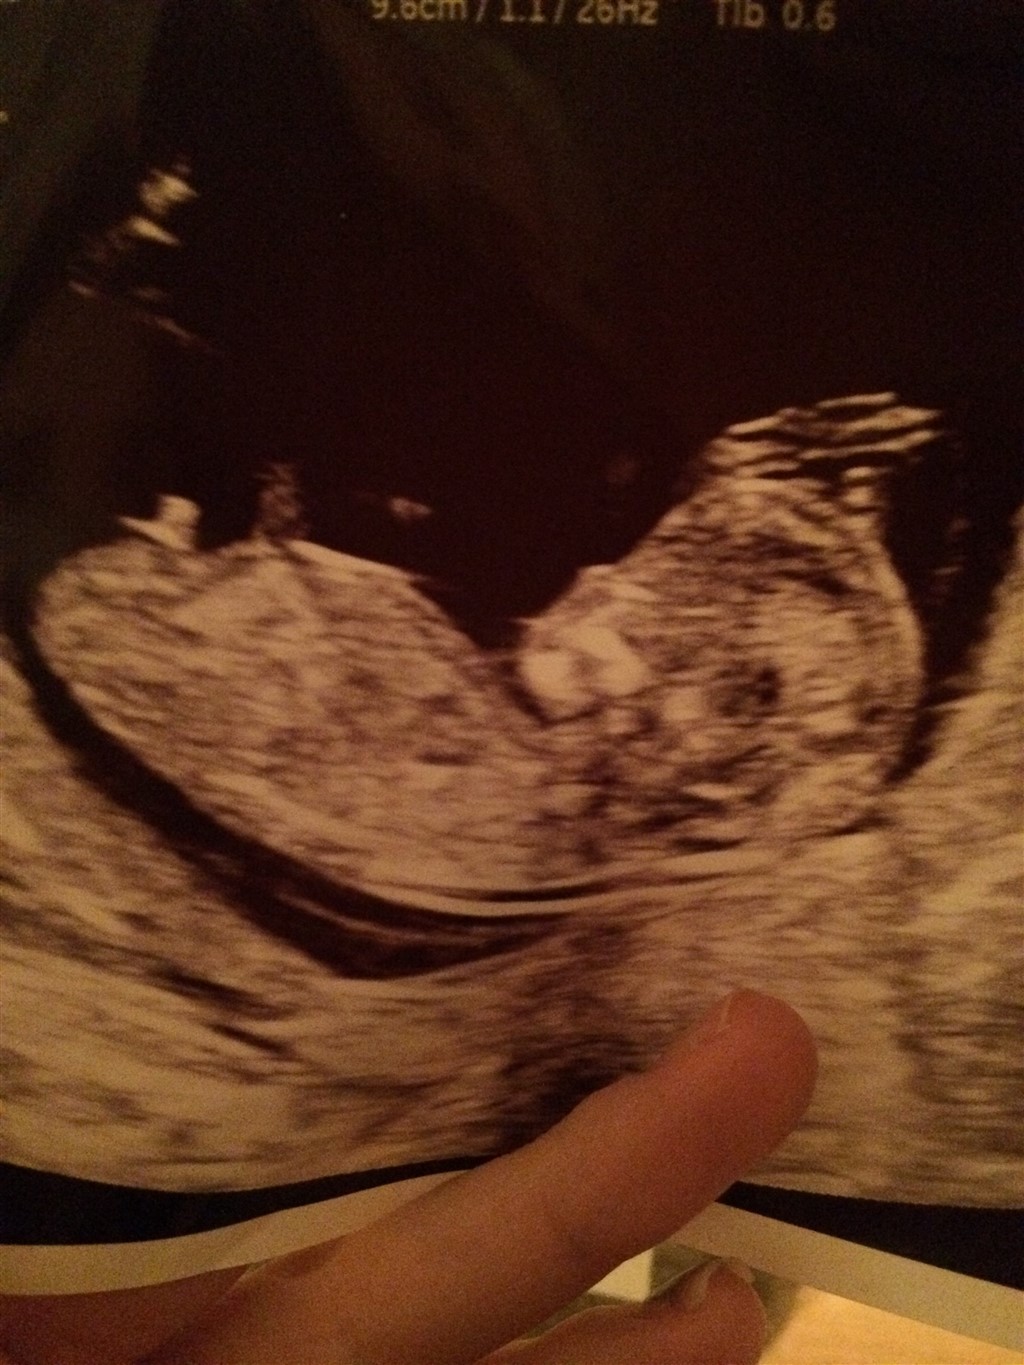

billedet er taget til NF 12+4. Kan det være andet end en dreng? Nogen hvis piger har set sådan ud tidligt i graviditeten ?

Det er en dreng.

Det ligner helt klart en dreng.

Vores pige troede man var en dreng frem til uge 16, hvor jeg fik endnu en scanning, men ja det ligner meget en dreng her

Jeg tror ikke den tap ændre sig �� Men man ved jo aldrig ��